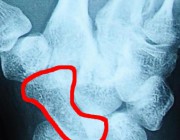

Переломы и несращения ладьевидной кости

Переломы ладьевидной кости занимают особое место в группе повреждений кисти. Данные травмы часто остаются незамеченными, однако в дальнейшем приводят к тяжелым нарушениям функции кисти, резким болям в области запястья, ограничению движений.